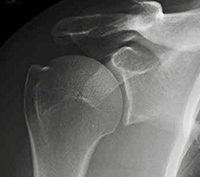

- X-rays - These images help to determine the extent of damage in your shoulder. They can show loss of the normal joint space between bones, flattening or irregularity in the shape of the bone, bone spurs and the ball riding high on the socket after chronic tendon tears.

Normal X-ray